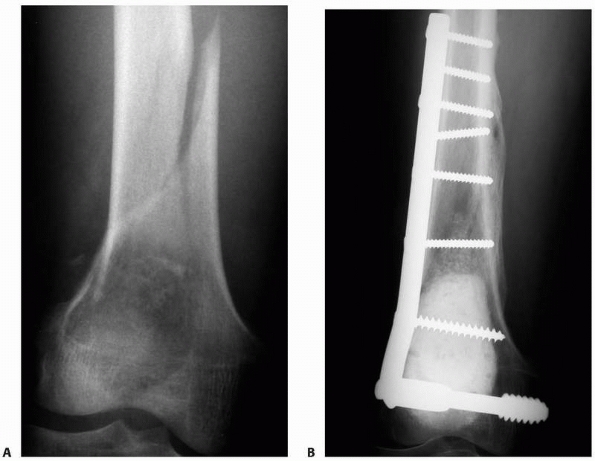

pathologic supracondylar femur fractures depends on the extent of local

bone destruction and the presence of additional lesions in the proximal

femur. The distal lesions can be a treatment challenge caused by

frequent comminution and poor bone stock, especially in older patients.

Options include lateral locking plate fixation supplemented with PMMA

or a modular distal femoral prosthesis.91

A retrograde nail has the drawback of potentially seeding the knee

joint with tumor while failing to provide fixation to the femoral neck

region. The locking plate provides stable fixation after curettage and

cementation of the metastatic lesion. The modular endoprosthesis is the

optimal choice for local control when there is massive destruction of

the femoral condyles, as it allows the lesion to be resected en bloc.24

![]() |

|

FIGURE 20-11 A.

Anteroposterior radiograph of the left femur in a 65-year-old man with metastatic renal cell carcinoma. He has a pathologic fracture through a small, osteolytic lesion in a high-stress area. B. Postoperative radiograph after stabilization of the fracture with a statically locked cephalomedullary femoral nail. Preoperative embolization was performed to minimize blood loss. Open curettage of the lesion was not performed because of its small size and the limited (less than 3 months) life span of the patient. |